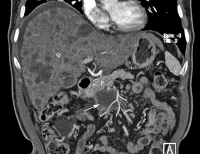

Klatskin-Tumor

Abbildung 6a-c: Klatskin-Tumor: Wert des leberspezifischen Kontrastmittels Gadoxetic Acid. (a) Die MRCP zeigt eine Striktur des D. hep. comm. (Pfeil). (b, c) Die Gadoxetic Acid-verstärkte T1-gewichtete Sequenz in der hepatobiliären Phase zeigt die Gallenwege kontrastmittelmarkiert und die umgebende Tumormanschette (Pfeilspitzen). Die Bilder sind trotz eines Metallartefakts (Stern) wegen eines Clips nach CHE beurteilbar.

Keywords: GastroenterologieHepatologieKlatskin-TumorMRCP